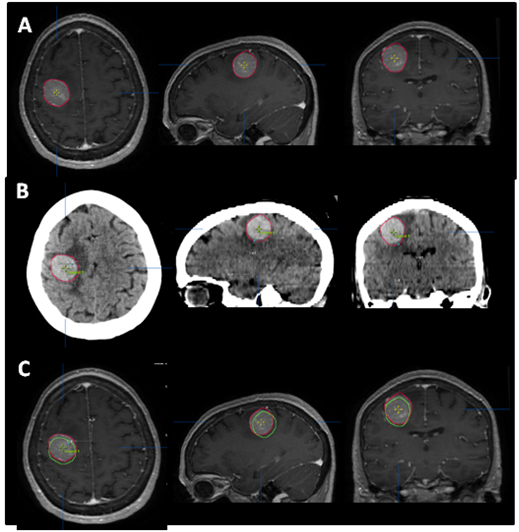

The patient is a 64year-old female who in 2004 was diagnosed with melanoma involving the skin of the right shoulder. This was treated with a wide local excision and sentinel lymph node biopsy. Pathology showed melanoma with a Breslow depth of 4.0mm with negative surgical margins. One sentinel lymph node was negative for metastasis. No adjuvant therapy was given. She did well until July 2012, when she developed progressive left upper extremity weakness and headaches. Brain MRI on August 5, 2012 showed a 2.8x2.5x2.8cm round mass, centered within the right pre-central gyrus, with diffuse, homogeneous, gadolinium contrast enhancement and significant surrounding vasogenic edema (Figure 1A) (Figure 1B). CT scan of the chest and abdomen demonstrated a 5.2x3.9cm mass in the right lower lobe of the lung along with two left lower lobe pulmonary nodules. She was started on dexamethasone (4mg q 6hours) and her headaches quickly resolved. The left upper extremity weakness also greatly improved.

Figure 1 (A) Pre-steroid T1 MRI with contrast. (B) Pre-steroid T2 MRI with FLAIR. (C) Post-steroid T1 MRI with contrast. (D) Post-steroid T2 MRI with FLAIR. Arrows depict reappearing sulci after steroid treatment.

The patient returned for simulation in preparation for frameless SRS on August 17, 2012, 12days after her initial brain MRI. CT simulation was performed using 2.4mm slice thickness. The Brain LAB Novalis Radio surgery System (iPlan RT V4.1, BrainLAB, Heimstetten, Germany) was used for the treatment planning and delivery. The original (pre-steroid) MRI from August 5, 2012 was registered and fused to the CT images for target delineation. The gross tumor volume (GTV) was contoured based on the isotropic 1mm thickness 3D MRI using a gadolinium enhanced T1 sequence (Figure 2A). However, when the GTV was superimposed on the CT images, it became clear that there was a significant mismatch. The hyperdense metastatic lesion was quite easily seen on the simulation CT images, even without IV contrast (Figure 2B). This prompted the decision to abort SRS. A repeat MRI was obtained on August 21, 2012 using identical imaging parameters. The new MRI showed stable enhancing right posterior cortical mass, but with improved surrounding vasogenic edema (Figure 1C) (Figure 1D). A second treatment plan was constructed based on the new MRI. The patient underwent SRS treatment on August 22, 2012. The final planning target volume (PTV) was 11.69cm3. Because of the relatively large volume (>10cm3) and eloquent location of the tumor, it was decided to prescribe 16Gy to the 90% isodose volume. Prior to dose delivery, target-localization was performed using the Brain LAB image-guided positioning system (ExacTrac V5.5.2). The treatment was delivered via 6 non-coplanar dynamic arcs, without difficulties. The patient tolerated SRS well.